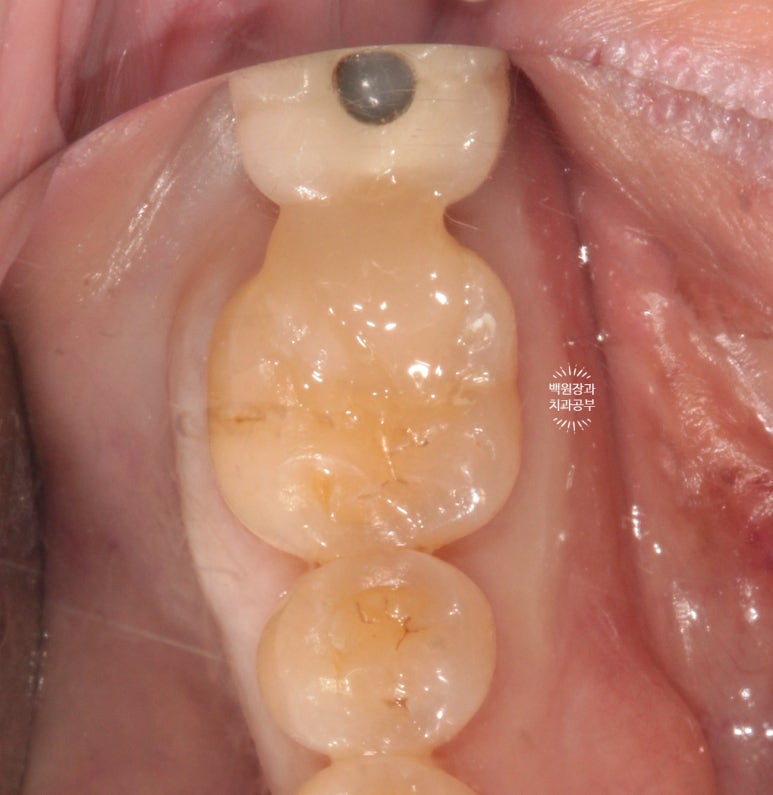

최대한 간결하고 예쁘게 지르코니아 크라운 지대치 삭제를 시행하였습니다.

치아의 길이가 너무 짧지 않았기 때문에, 잇몸 성형을 해주지 않아도 되는 경우였어요.

옆에서 보았을 때도 모양이 깔끔합니다.

당연한 과정이지만, 교합이 형성되도록 물었을 때 제작될 크라운의 두께가 충분한지도 반드시 확인해야합니다.

너무 얇은 지르코니아 크라운을 붙여드리면 금방 깨질 수 있으니깐요.

그리고 만약 이 두께가 충분하지 않아 보이면 치아를 더 깎아내야되겠죠? 더 깎아내면 너~무 치아가 조금 남을 것으로 예상될 때는 잇몸 성형을 해주어야 되겠죠? (간단한 원리입니다.)

그리고 사람 턱은 캐스터네츠가 아니기 때문에, 딱딱딱 물었을 때 뿐만 아니라

지글지글 양 옆으로 갈았을때, 턱을 앞으로 내밀었을 때를 모두 재연하여 확인을 해야합니다.

저렇게 깎여져 있는 채로 집에 가실 수 없죠!

임시치아를 제작하여 접착 후 귀가하시게 되는데요,